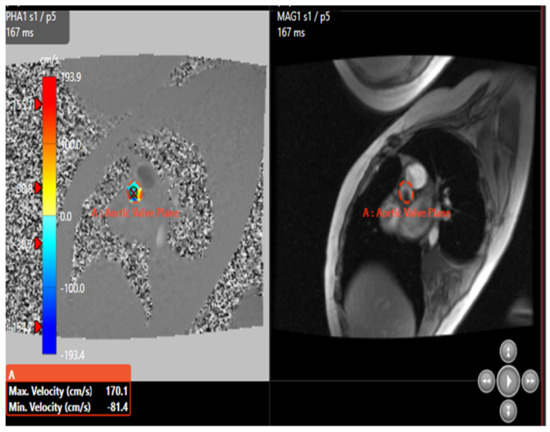

6.5. Cardiovascular Solution with Pie Medical Imaging “Caas 4D Flow”

Our clinical case of aortic coarctation led to narrowing of the aortic valve with shone syndrome (two single-pillar valvular leaflet). In this case, the 5D model for the valve structure is corrosive, given the morphological dissection of the valve leaflet. The definition of the inputs and outputs, as well as the conditions of the limits of the aortic valve, are complicated because the valve acts as a blood pump. For this reason, the use of this research product that enhances the fifth dimension of 2D blood flow is used to predict and simulate the occlusion rate at the aortic valve level. Caas MR 4D Flow allows examining the 2D blood flow by reformatting planes in a 3D volume retrospectively. Additional plans can be placed on the 3D volume’s middle side. Standard 2D flow parameters, such as the flow rate, forward flow, and back flow, can be measured using 2D flow analysis. In addition, an extreme eccentric flow measurement in a plane was calculated based on the method of moving the flow [39]. The contour is redefined on its initial contour, initially shown by the Caas MR 4D flow in Figure 23.

Figure 23.

Contour accuracy of the aortic valve.

The displacement of the flow is defined as the distance between the center of the light and the “center of velocity” of the flow, normalized with respect to the diameter of the light. The center of velocity (Cvel) was calculated as the average position of the pixels of the light (ri, where i = x, y, z), weighted by the velocity information (vi) as follows:

where i represents the pixels within the vessel’s outline, and j represents the spatial orientation of the pixels relative to the location of the center of the vessel. This method is described in more detail in the literature [39,40]. The flow displacement was calculated for the maximum systolic phase only, as shown in Figure 24. The maximum systolic phase was determined for each transmitter plane and determined using the time slot at the top of the 2D graph. The maximum systolic phase was indicated as a marker of phase slider. A description of the measurements is presented in Table 6.

Figure 24.

Simulation of flow within the aortic valve.

Antegrade flow is used to quantify the blood pumped in the positive direction measured on the plane in a cardiac cycle, while retrograde flow is used to measure the amount of blood pumped in the positive direction on the plane in a cardiac cycle. The pump function of the valve was measured using forward flow to the back. The regurgitation fraction is the ratio of the backward flow (mL) to the forward flow (mL) and the area under the curve of the negative (backward flow) portion of the cardiac cycle. The gap between the vessel’s axis and the center of the eccentric flow was normalized to the total size of the vessel to enhance the heat transfer displacement [39]. It is possible to draw from this section the interest of studying the fifth dimension of blood flow to quantify and estimate both the regurgitation rate as well as a simulation of the minimum negative sign velocity of −81.4 (cm/s) to predict stenosis at the level of the aortic valve.